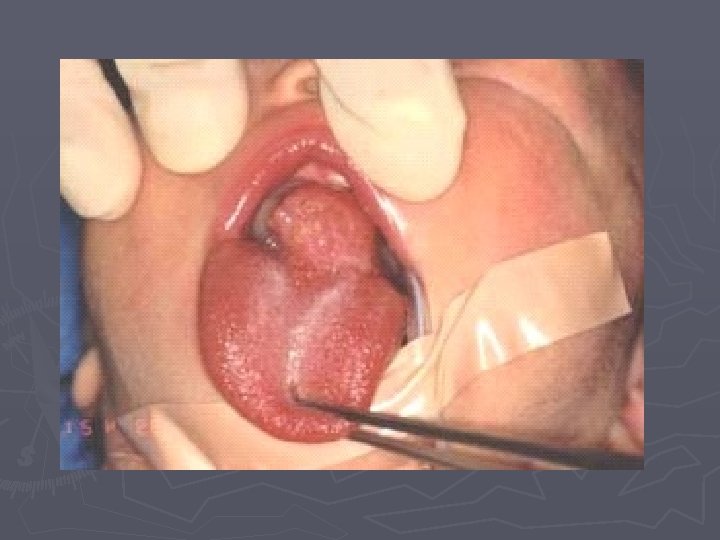

DISPLASIA ► Cuando la displasia afecta todo el espesor del epitelio se habla de un carcinoma in situ, esto quiere decir que la neoplasia esta limitada al epitelio y no ha sobrepasado la membana basal. ► En la actualidad se cambia el termino de displasia por el de Neoplasia intraepitelial

Trastornos predisponentes no hereditarios ► Proliferaciones regenerativas, hiperplásicas y displásicas…suelo fértil para el origen de un tumor maligno. Ej: Displasia de cérvix- CA Metaplasia y displasia de mucosa bronquial en fumadores. . Ca broncogénico.